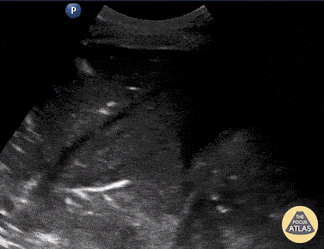

Patient presented with septic shock. POCUS was used to assess for etiology in this hemodynamically unstable patient. Shown here is a lung US windows (patients LLL) revealing a consolidation pattern with echoginicity similar to liver, referred to as “hepatization” of the lung. These findings are consistent with a diagnosis of pneumonia. Johannes Achenbach